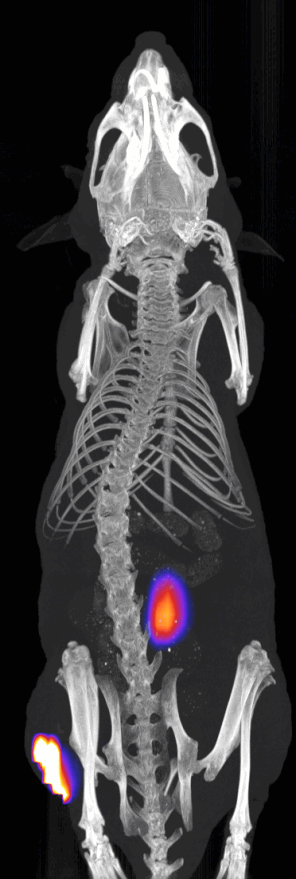

The InSyTe FLECT/CT is a dual-modality, preclinical molecular imaging platform that combines complete angle fluorescence tomography with X-ray CT. Fluorescence data is acquired in two modes; 2D reflectance or in 360° (complete angle), acquiring optical images with InSyTe FLECT/CT. Optimized for detection of near infrared (NIR) fluorescence to enable deep tissue imaging capability in vivo, the InSyTe FLECT/CT is compatible with a wide variety of commercially available NIR-labelled probes and fluorescent dyes, allowing for investigation of a broad spectrum of research areas. Combined with the inline X-ray CT subsystem, the InSyTe FLECT/CT performs noninvasive, radioisotope-free, 3D tomographic imaging with anatomical reference and is easily installed in a standard research laboratory or preclinical imaging facility.